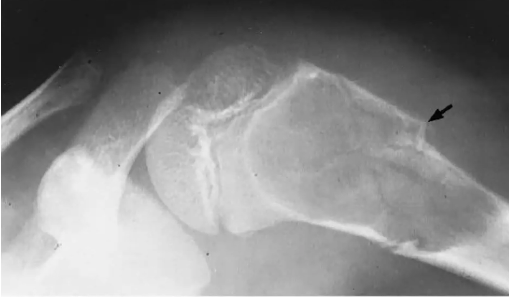

malin 2e plus fréquent, très agressif

o Réaction périostée : spiculée = sunburst apparence

o Sclérotique/lytique ou mixte

o Expansion dans les tissus mous : cumulus cloud

o Triangle de Coddman : signe que le cortex est brisé

o NE TRAVERSE PAS LA PLAQUE DE CROISSANCE NON OSSIFIÉE ou l’articulation : car distribution hématologique VS infection ne respecte PAS la plaque de croissance